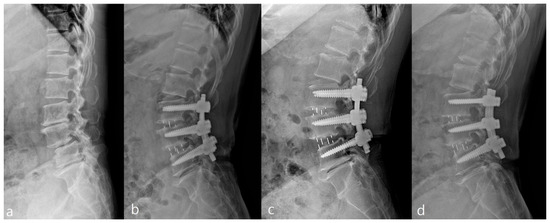

Transforaminal Endoscopic Lumbar Foraminotomy for Juxta-Fusional Foraminal Stenosis

by Yong Ahn and Han-Byeol Park

J. Clin. Med. 2023, 12(17), 5745; https://doi.org/10.3390/jcm12175745 - 4 Sep 2023

Adjacent segment foraminal stenosis is a significant adverse event of lumbar fusion. Conventional revision surgery with an extended fusion segment may result in considerable surgical morbidity owing to extensive tissue injury. Transforaminal endoscopic lumbar foraminotomy (TELF) is a minimally invasive surgical approach for [...] Read more.

Adjacent segment foraminal stenosis is a significant adverse event of lumbar fusion. Conventional revision surgery with an extended fusion segment may result in considerable surgical morbidity owing to extensive tissue injury. Transforaminal endoscopic lumbar foraminotomy (TELF) is a minimally invasive surgical approach for symptomatic foraminal stenosis. This study aimed to demonstrate the surgical technique and clinical outcomes of TELF for the treatment of juxta-fusional foraminal stenosis. Full-scale foraminal decompression was performed via a transforaminal endoscopic approach under local anesthesia. A total of 22 consecutive patients who had undergone TELF were evaluated. The included patients had unilateral foraminal stenosis at the juxta-fusional level of the previous fusion surgery, intractable lumbar radicular pain despite at least six months of non-operative treatment, and verified pain focus by imaging and selective nerve root block. The visual analog scale and Oswestry Disability Index scores significantly improved after the two-year follow-up period. The modified MacNab criteria were excellent in six patients (27.27%), good in 12 (55.55%), fair in two (9.09%), and poor in two (9.09%), with a 90.91% symptomatic improvement rate. No significant surgical complications were observed. The minimally invasive TELF is effective for juxta-fusional foraminal stenosis. Full article

(This article belongs to the Section General Surgery)

Show Figures

Graphical abstract